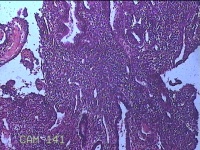

宫腔内容物

性别

女

年龄

41岁

临床诊断

异常子宫出血(无排卵型子宫出血) 子宫肌瘤

一般病史

阴道流血12天。

标本名称

大体所见

灰白暗红色不规则碎组织2.5x2x0.8cm一堆。